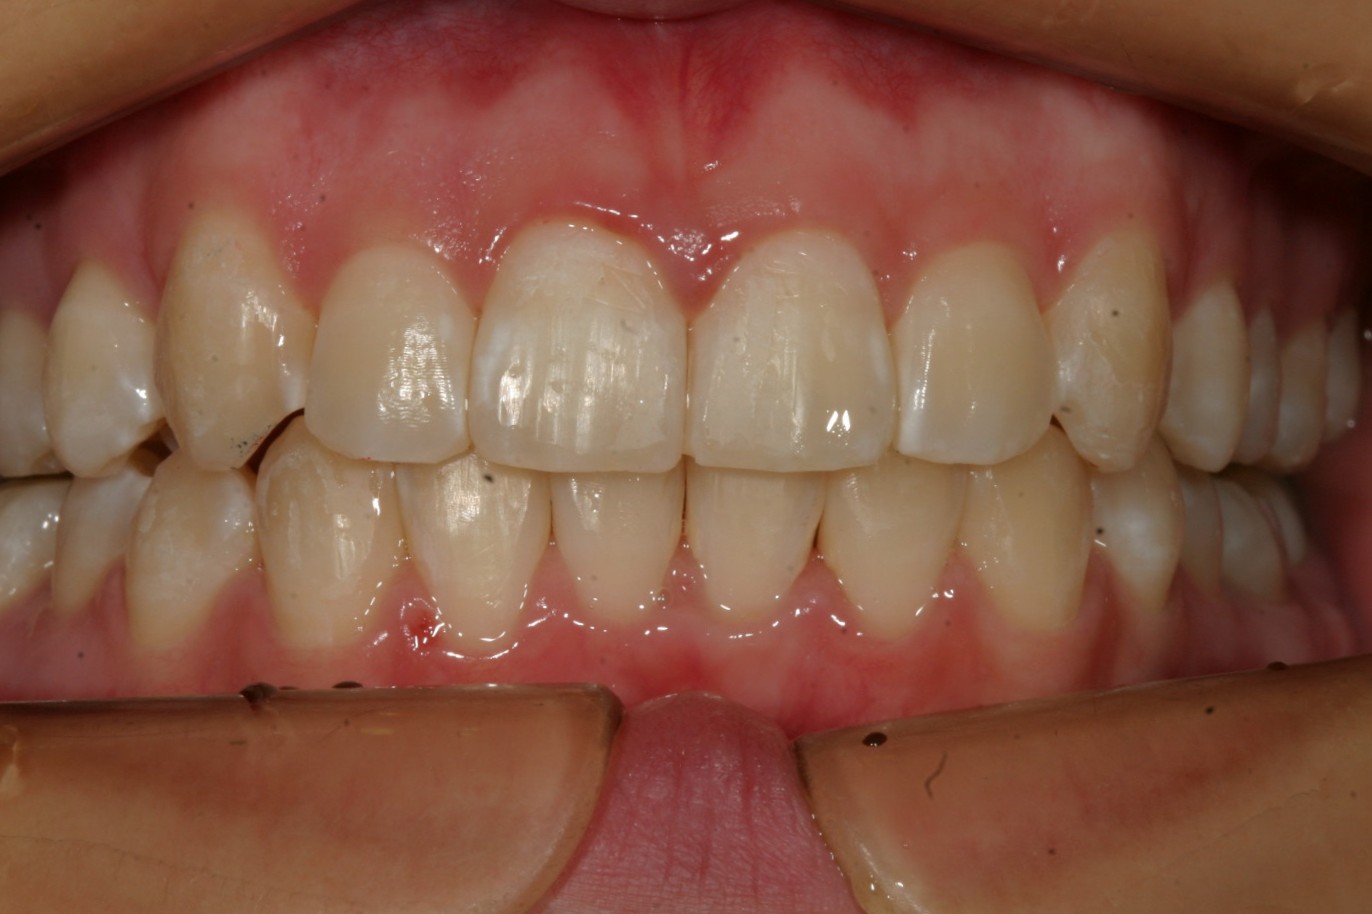

抜歯無しでここまで改善致しました。

下顎のガタガタも綺麗になりました。

最高の側面観です。

このケースは非抜歯で犬歯の唇側転移を改善致しました。

下顎も結構ガタガタしてましたが患者様の熱心な頑張りで僅か1年4カ月でこの様に綺麗に改善しました。

インビザラインは上手く治らないとおっしゃる患者様も居られるようですが患者様の頑張り次第でここまで改善できると言う証明です。